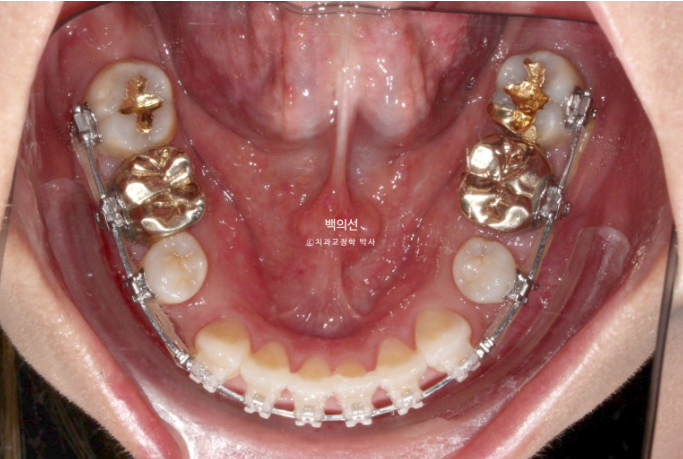

브릿지를 잘라낸 모습입니다.

클리피씨 치료를 선택하셨고 치료에 들어갔습니다.